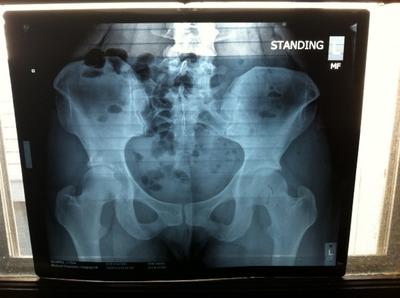

Pelvic XRay Standing

Here are the two X-Rays I have. They were taken back in the beginning of March of this year. Thank you for your time!

I take it you took these digi photos yourself of the original X-rays. Could you please take a spot picture of the right hip - get up close - and the lateral lumbo-sacral joint. These are not of diagnositic quality. Send them to brlewis@mweb.co.za without reducing the size of the images.

I can see there's something going on the right hip, but not what.

There is a huge amount of rotation of the lumbar vertebrae, so clearly this is a back and hip condition. Really two different conditions that feed off each other.